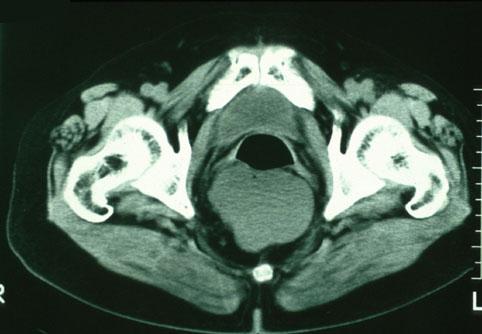

A case of rectal leiomyosarcoma showing the diagnostic usefulness of computed tomography (CT).

Malignant non-epithelilal tumors/Leiomyosarcoma (including GIST)

Location

Large intestine(Colon)/Rectum

CT

Size

35 - 40